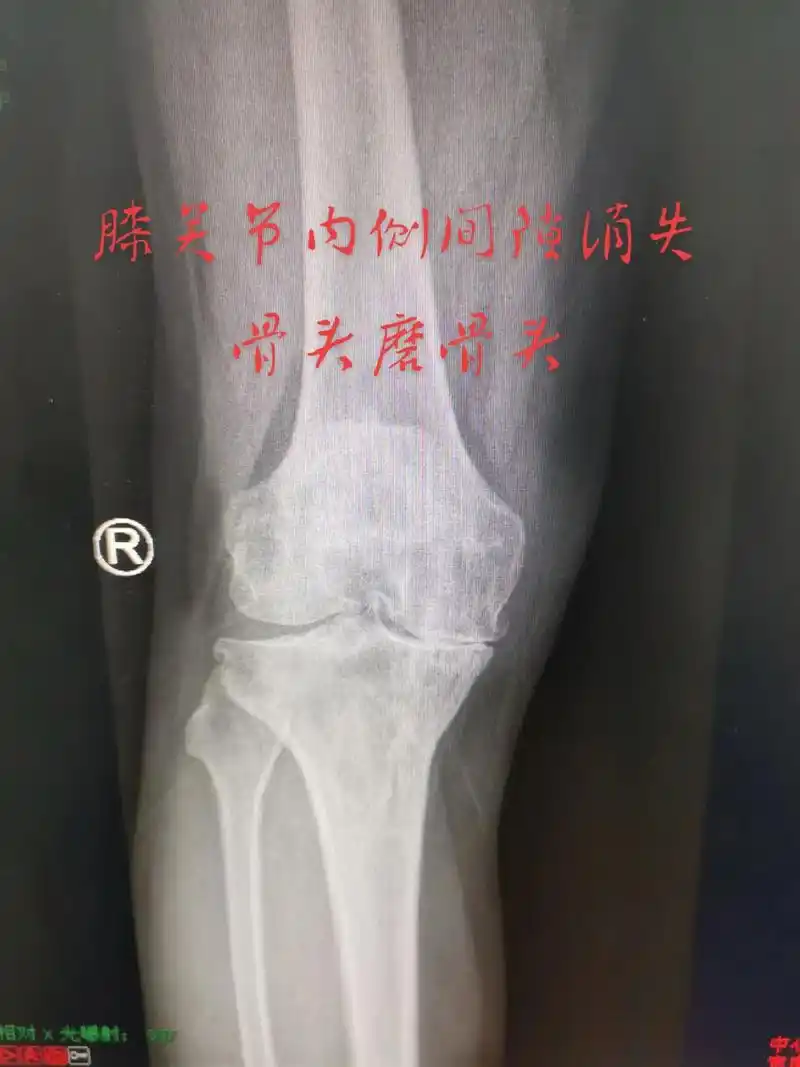

各位高手请帮忙看下一张膝关节平片